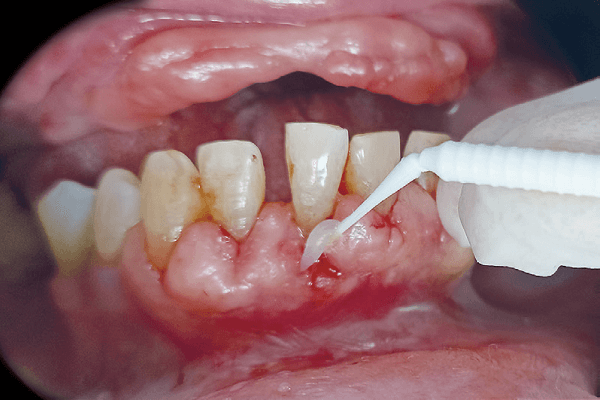

Infecção e cicatrização demorada

A cicatrização mais demorada em pacientes diabéticos resulta de uma interação de fatores fisiológicos alterados pela condição metabólica.

A resposta imunológica comprometida pela diabetes reduz a capacidade do organismo de combater infecções e coordenar eficientemente a cicatrização.

Além disso, a microcirculação prejudicada devido a danos nos vasos sanguíneos impede a entrega adequada de nutrientes e oxigênio às áreas feridas.

Alterações no metabolismo do colágeno, uma proteína essencial na formação de tecido cicatricial, comprometem a qualidade do tecido regenerado.

A presença persistente de altos níveis de glicose no sangue interage negativamente com processos celulares, prejudicando a formação adequada do tecido cicatricial.

Em resumo, a propensão aumentada a infecções em pacientes diabéticos, combinada com a dificuldade no controle glicêmico, contribui para complicações pós-operatórias que prolongam ainda mais o processo de cicatrização.